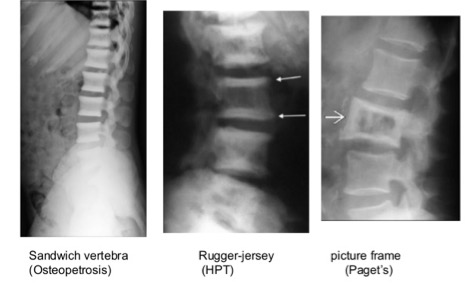

Rugger jersey spine:

Differentials include:

- Renal osteodystrophy

- Osteopetrosis & myelofibrosis

Osteopetrosis: Hamburger or sandwich vertebra is a classic sign

Ivory vertebra sign: Increase in opacity of vertebral body that retains its size & contours, with no change in the opacity & size of adjacent intervertebral disc.

- Osteoblastic metastases

- Lymphoma

- Paget disease

- Fluorosis

- Osteopetrosis